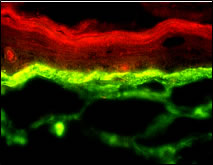

Ein Wirkstoff auf Malzbasis, Basaline , ist in der Lage, als 2%ige Creme viermalig über 10 Tage topisch angewendet, die Lamininsynthese in der Basalmembran des Hautmodells zu stimulieren (Abb. 6).

Abb. 6: Immunfluoreszenz-Färbung von Laminin in der Basalmembran des Ganzhautmodells nach viermaliger Behandlung mit 2%iger Basaline -Creme über 10 Tage.

Placebocreme:

|

Basaline-Creme:

|